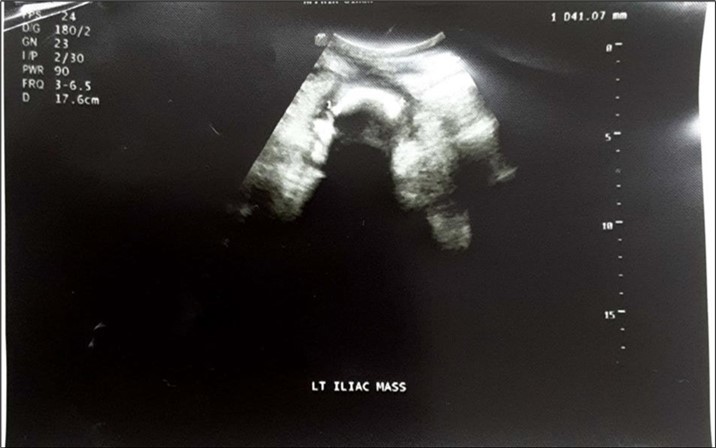

An impression of an intestinal obstruction due to postoperative adhesions was made. An abdominal X-ray done showed no obvious signs of bowel dilatation but an ill-defined opacification in the area of the left lumbar region (Figure 1). An ultrasonography done showed an echogenic mass in the left iliac region measuring about 4.1cm in diameter. There was no flow on colour doppler interrogation (Figure 2). At this point a diagnosis of foreign body was queried. The patient was counselled and prepared for exploratory laparotomy.

Figure 2.Abdominopelvic USG: An echogenic mass in the left iliac region measuring about 4.1cm in diameter. There was no flow on colour doppler interrogation.

Abdominopelvic USG: An echogenic mass in the left iliac region measuring about 4.1cm in diameter. There was no flow on colour doppler interrogation.